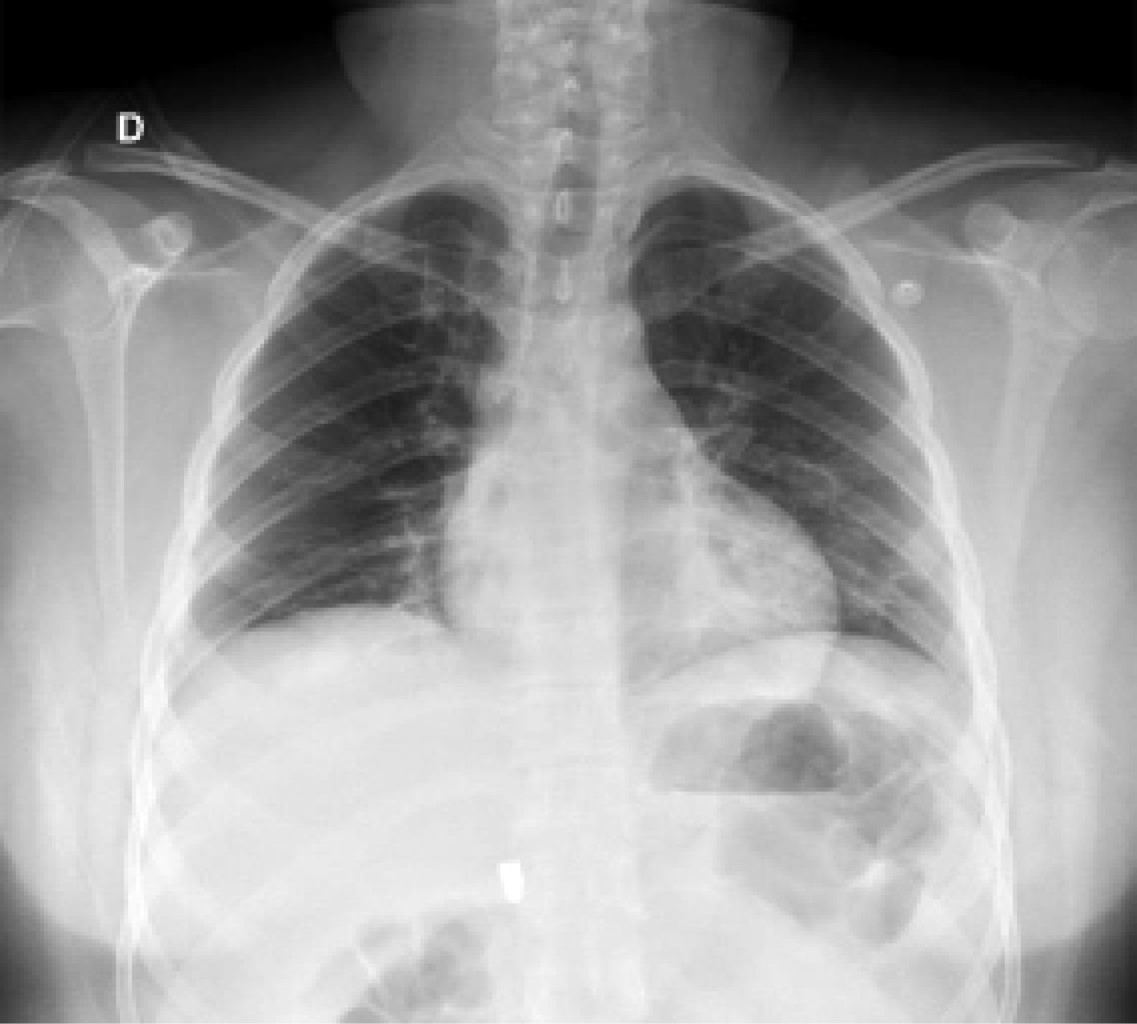

On physical examination, her vital signs were as follows: heart rate of 74 beats/minute; blood pressure of 98/67 mmHg; respiratory rate of 19/min; temperature of 36o C; and oxygen saturation of 98%. The chest showed a PAF entry orifice in the upper outer quadrant of the right breast (Figure 1), and the lung fields were well-ventilated. The abdomen was flat, with peristalsis, soft and painless to palpation. The blood cytology reported a hemoglobin of 12.8 g/dL, hematocrit of 36.4%, and white blood cells of 6,400/ml. The chest X-ray ruled out pneumothorax (Figure 2). A CT scan of the thorax and abdomen showed a metallic foreign body lodged in the right parasagittal line at the level of the 12th thoracic vertebra (Figure 3), without pulmonary or diaphragmatic lesion (Figures 4 and 5); in the abdomen, a PAF tract was observed with a 12 cm by 2.3 cm grade IV liver lesion in segments IV, VII and VIII of Couinaud (Figure 5), scarce free fluid, without lesion of any other organ (Figures 3, 5 and 6). Twenty-four hours later, a control CT scan was performed, showing the liver lesion without subcapsular collection or active extravasation on the application of contrast medium, without an increase of free fluid. Given the correlation of these findings with clinical stability, the patient was discharged on the fourth day of her admission. She did not have any complications one month after her discharge.

Figure 3

Figure 4

Figure 5

Figure 6